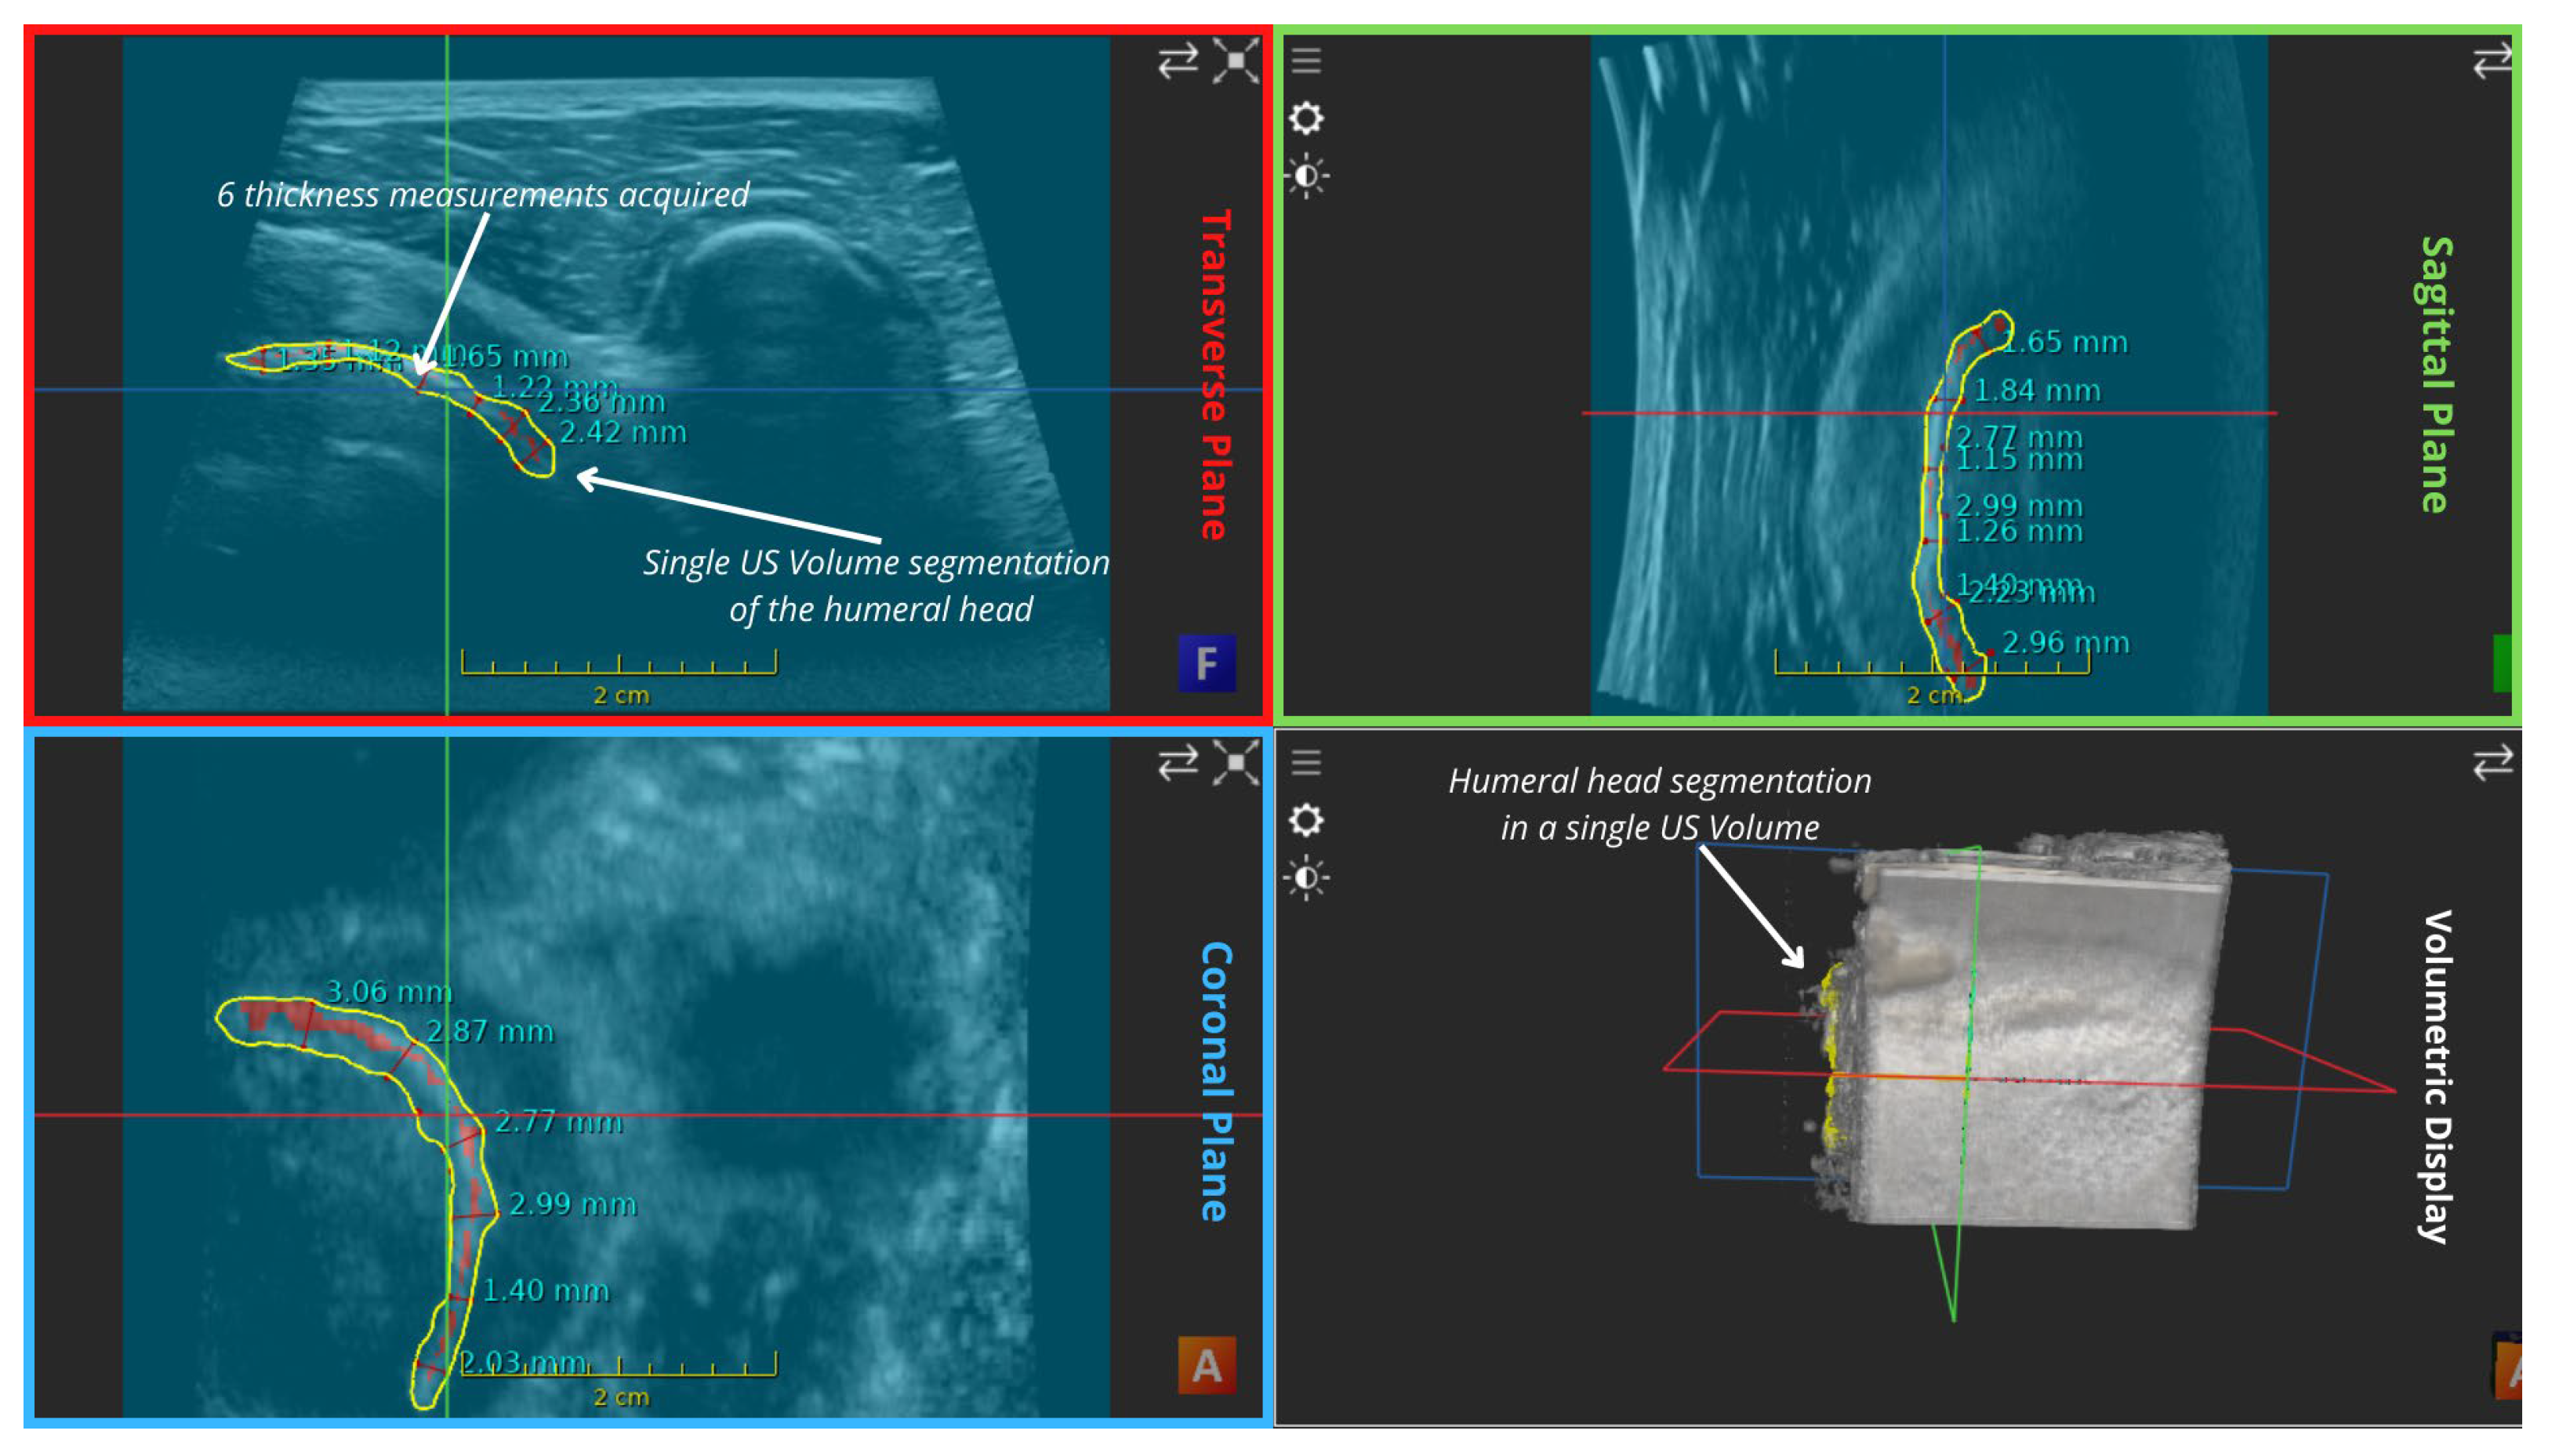

| Mean Values (mm) | Transverse Plane | Sagittal Plane | Coronal Plane | Overall |

|---|---|---|---|---|

| Thickness in mosaic | 2.675 | 2.481666667 | 2.755 | 2.637222 |

| Thickness in a single volume | 1.686666667 | 1.758333333 | 2.52 | 1.988333 |

| Reconstruction Error (Thickness) | 0.988333333 | 0.723333333 | 0.235 | 0.648889 |